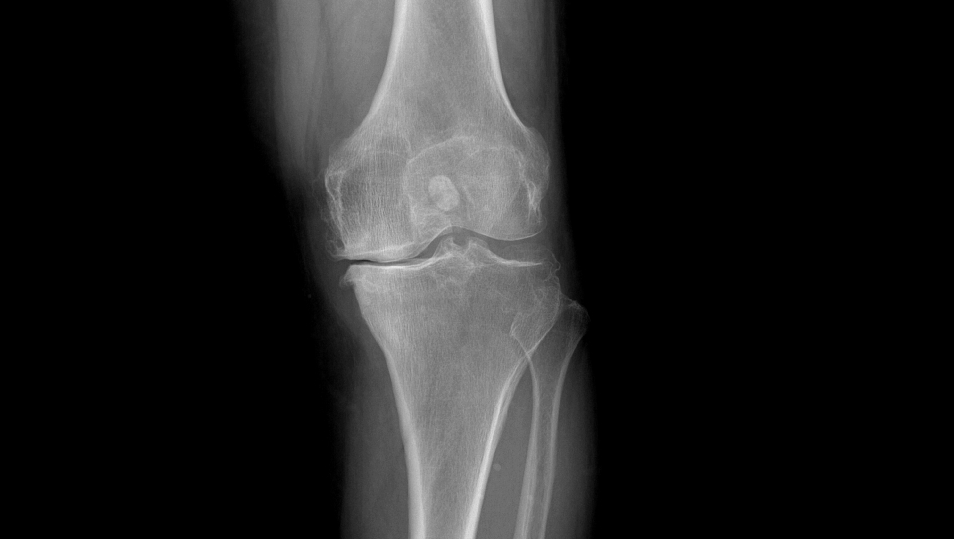

患者术前VS术后对比

①站立位X光片中显示关节间隙消失或极度狭窄

当膝关节由于各种原因,如晚期膝骨关节炎、类风湿关节炎等,导致关节显著破坏,并出现疼痛、活动障碍等症状,通过药物、理疗等手段医治无效时,则可以考虑接受人工膝关节置换手术。